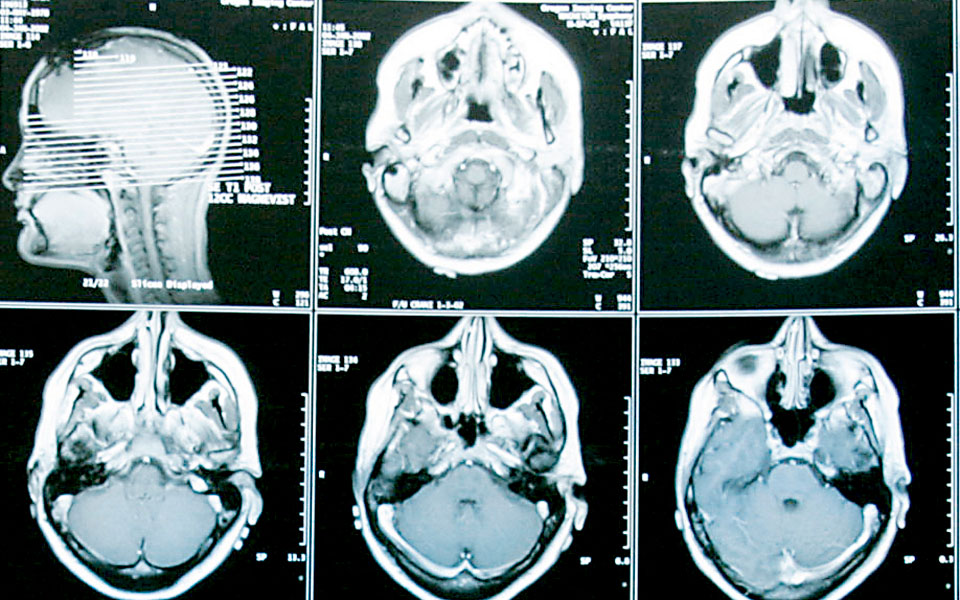

Υπάρχουν πολλοί διαφορετικοί τύποι καρκίνου του εγκεφάλου, και το γλοιοβλάστωμα είναι η πιο συνηθισμένη μορφή που εμφανίζεται σε ενηλίκους και η πιο δύσκολα θεραπεύσιμη.

Αναπτύσσεται ραγδαία και εξαπλώνεται στον εγκέφαλο με αποτέλεσμα να είναι δύσκολο να καταλάβει κανείς πού τελειώνει ο όγκος και πού ξεκινά ο υγιής ιστός. Η πρόσφατη έρευνα όμως δείχνει ότι μια θεραπεία που περιλαμβάνει τη χρήση του ιού Ζίκα, μπορεί να εξουδετερώσει τα ανθεκτικά στις υπάρχουσες μορφές θεραπείας καρκινικά κύτταρα.